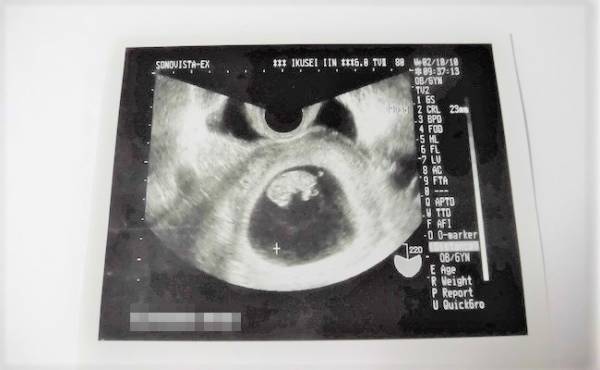

胎動を感じる瞬間。それは、命が宿っていることを再認識できるとても素敵な瞬間です。最初は小さな動きだったものが、だんだん大きな動きになり、より実感が増していきます。そんななか、私は不思議な胎動を体験しました。その正体とは……。

私が最初に感じた胎動は、ぐるんと腸の中で何かが動いたかのような感覚でした。その感覚を頻繁に感じるようになり、「これは胎動だ!」と気付き、とても感激したことを覚えています。

でも胎動によって、おなかの中で赤ちゃんが生きていると実感できるようになりました。ところがあるとき、「ポクン、ポクン」という定期的な胎動が続くようになり、少し心配になってしまいました。